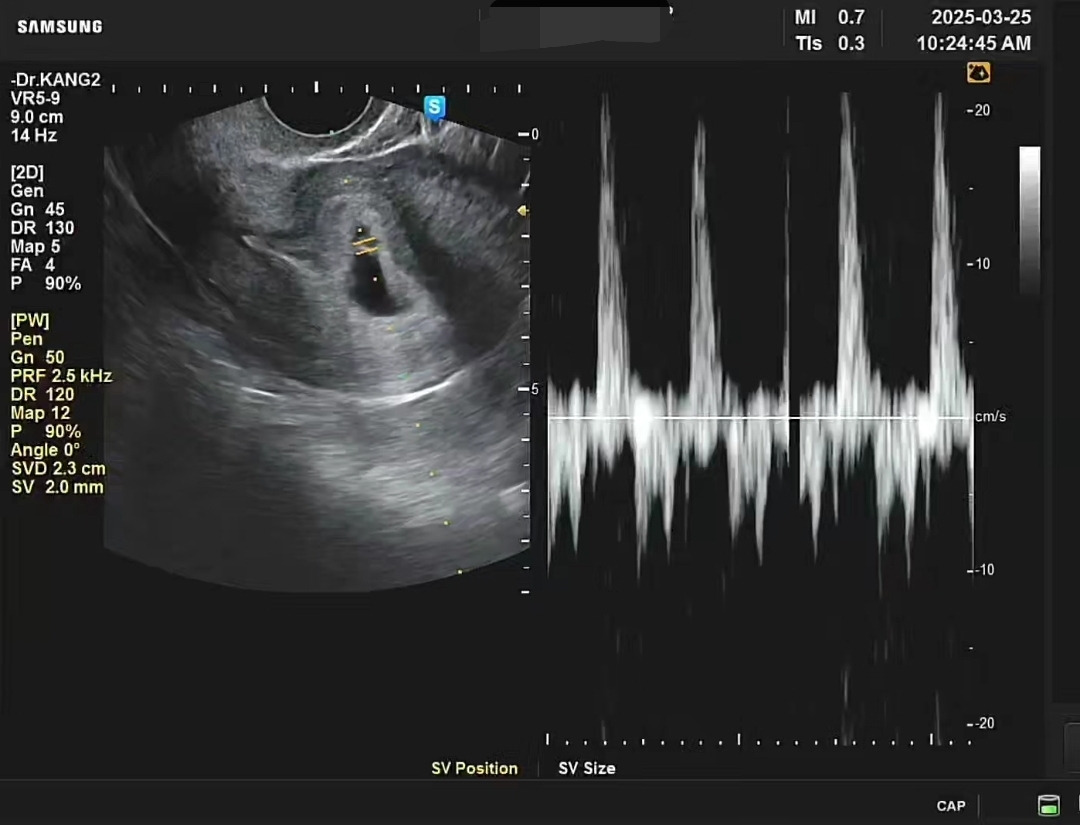

초음파를 보았다. 작은 콩이 움찔움찔 움직였다. 소리도 들었다. 몸속 잡음에 섞인 선명한 박동소리.

도동, 도동, 도동, 도동.

일정하게 잘 뛰고 있었다. 너무 감격해 우는 산모도 많다는데 나는 그렇지는 않았다. 그저 다행이란 생각, 역시 잘 있어주어 기특하다는 감각.

간호사 선생님이 진료실 앞에서 대기하던 남편을 불러들였다. 남편도 라이브로 아기 심장 소리를 들었다. 연애 7년, 결혼 7년. 도합 14년 차에 만난 첫 생명의 소리였다. 아기 크기는 이제야 0.55cm. 6주 2일이라고 했다. 그 작은 것이 열심히 뛰고 있었다. 펄떡펄떡, 팔딱팔딱.

초음파 영상을 다운받아 소식을 기다리던 어른들께 보내드렸다. 규칙적으로 잘 뛰는 아기 심장소리에 모두가 기뻐해주었다. 물론 가장 기쁜 건 우리 부부였다. 신기하고, 벅차고, 기특하고, 용했다.